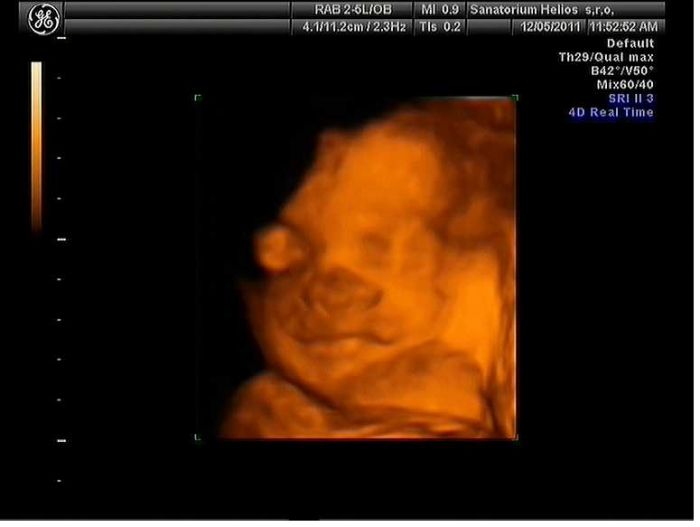

..tady jeste prikladam jediny dve povedeny fotky toho naseho drobecka